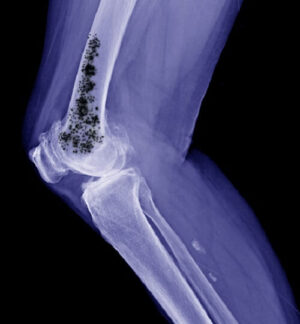

У большинства пациентов, энхондрома, причины развития которой до сих пор до конца не выяснены, ограничена и не затрагивает соседние ткани. На начальных этапах патологии характерные признаки, как правило, не проявляются, пациент не обращается за специализированной медицинской помощью, и новообразование обнаруживается случайно, в ходе рентгенографии по поводу другого нарушения. Указывающие на наличие энхондромы выраженные боли, частые переломы, обусловленные повышенной хрупкостью костных тканей, отмечаются только при значительном увеличении размера опухоли.

- рентгенографии — выявление новообразования, развивающегося в трубчатых костях конечностей;